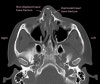

CT : 코뼈 골절(Nasal fracture)